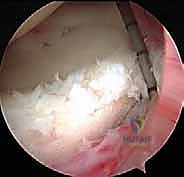

هو تقنية جراحية طفيفة التوغل (Minimally Invasive) تعتمد على إحداث شقوق صغيرة جدًا (لا تتجاوز نصف سنتيمتر). يتم إدخال كاميرا دقيقة وعالية الدقة (Arthroscopy) متصلة بشاشة عرض 4K، مما يمنح الجراح رؤية مكبرة وواضحة تمامًا لكل تفاصيل المفصل من الداخل. من خلال شقوق أخرى، يتم إدخال أدوات جراحية دقيقة جدًا لإجراء الإصلاح.

3. الاستكشاف التشخيصي بالمنظار:

قبل البدء بالإصلاح، يقوم الجراح بجولة استكشافية شاملة داخل المفصل. يتم تقييم الشفة الأمامية، الخلفية، العلوية، الغضاريف المفصلية، وأوتار الكفة المدورة للتأكد من عدم وجود إصابات مصاحبة خفية.

4. تحضير موقع الإصلاح (Preparation):

يتم استخدام أدوات دقيقة لتنظيف الأنسجة التالفة وإزالة أي ندبات. الخطوة الأهم هي "تخشين" (Abrasion) حافة عظم التجويف الحقاني الخلفي. هذا التخشين يهدف إلى إحداث نزيف دقيق يحفز عملية التئام الشفة الممزقة بالعظم لاحقًا.

5. زرع الخطاطيف العظمية (Suture Anchors Insertion):

يتم زرع خطاطيف دقيقة جدًا (غالبًا ما تكون مصنوعة من مواد قابلة للامتصاص الحيوي أو مادة PEEK القوية) في حافة عظم التجويف الحقاني الخلفي. هذه الخطاطيف محملة بخيوط جراحية فائقة القوة.

6. خياطة الشفة وشد المحفظة (Capsulolabral Shift & Repair):

باستخدام أدوات تمرير الخيوط المتطورة، يقوم الدكتور هطيف بتمرير الخيوط عبر المحفظة المفصلية المرتخية والشفة الحقانية المتمزقة. يتم بعد ذلك سحب هذه الأنسجة وربط الخيوط بعقد جراحية محكمة.

هذه الخطوة المزدوجة تحقق هدفين: إعادة تثبيت الشفة في مكانها التشريحي الصحيح (بناء مصد خلفي يمنع خروج العظم)،